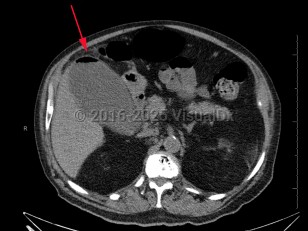

Imaging Studies image of Emphysematous cholecystitis - imageId=8355357. Click to open in gallery.  caption: '<span>Image from CT scan demonstrates a distended gallbladder with air in the wall. The patient also had gallstones. </span>'

Image from CT scan demonstrates a distended gallbladder with air in the wall. The patient also had gallstones.